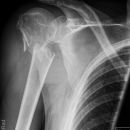

Schulterluxation